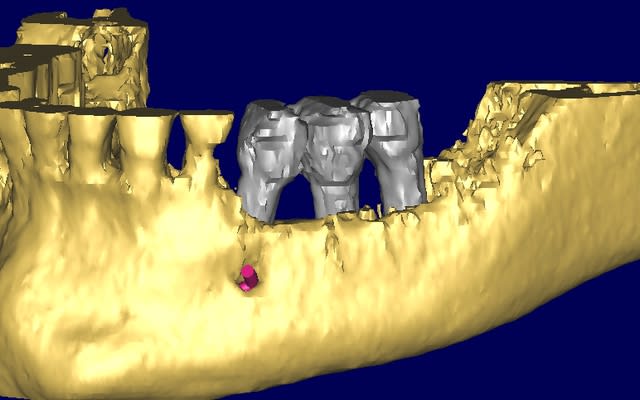

quelques images en 3 D...

Bernard 3d uwkkkv - Eugenol

Bernard 3d  2  cbjwkc - Eugenol

Bernard 3d1 tranjs - Eugenol

Bernard 3d2 egud68 - Eugenol

Bernard 3d3 kd3ilv - Eugenol

Bernard 3d4 iyukqz - Eugenol

Bernard cross section apfhj5 - Eugenol

Bernard cross section  2  ctt7jw - Eugenol

Bernard overview edbft1 - Eugenol

Bernard overview  2  nlgyly - Eugenol

Bernard panoramic l8hei0 - Eugenol